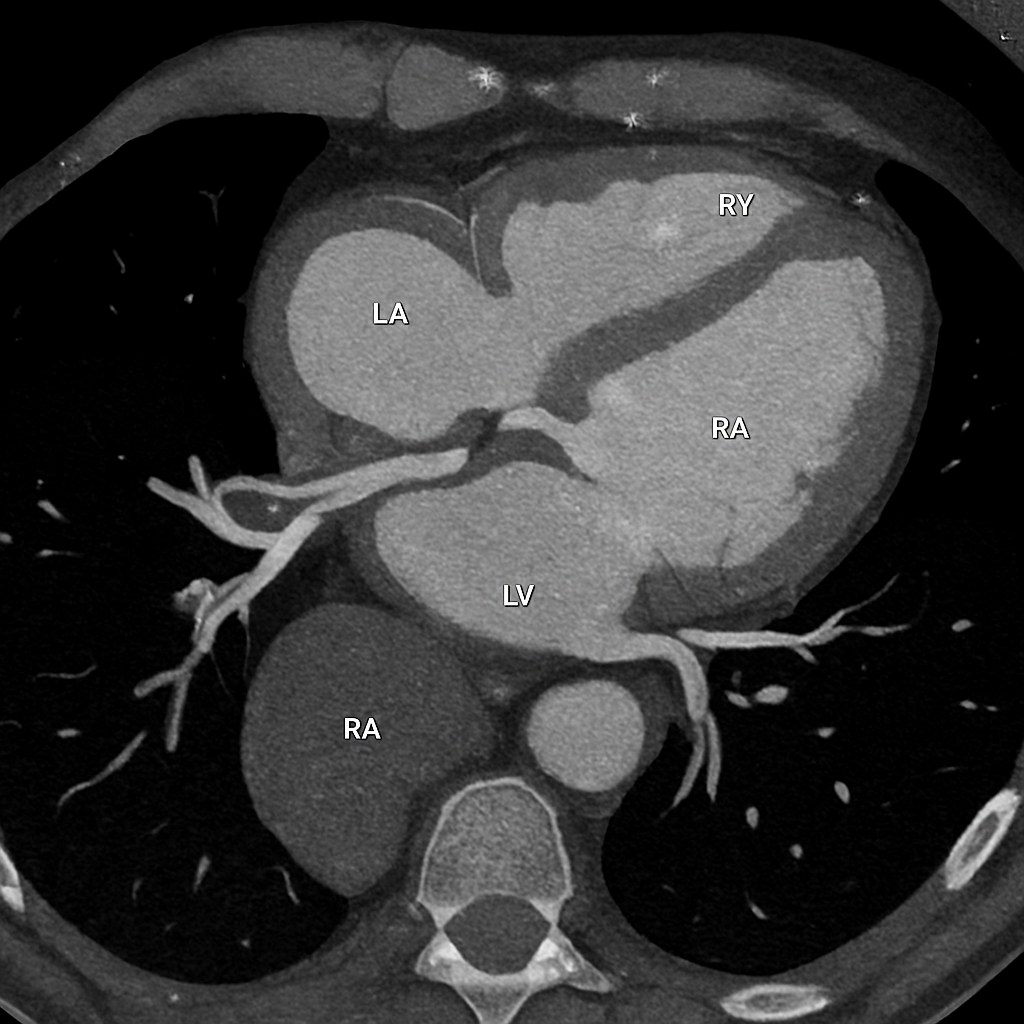

AI-generated comprehensive cardiac phantom with all four chambers, valves, coronary arteries, great vessels,...